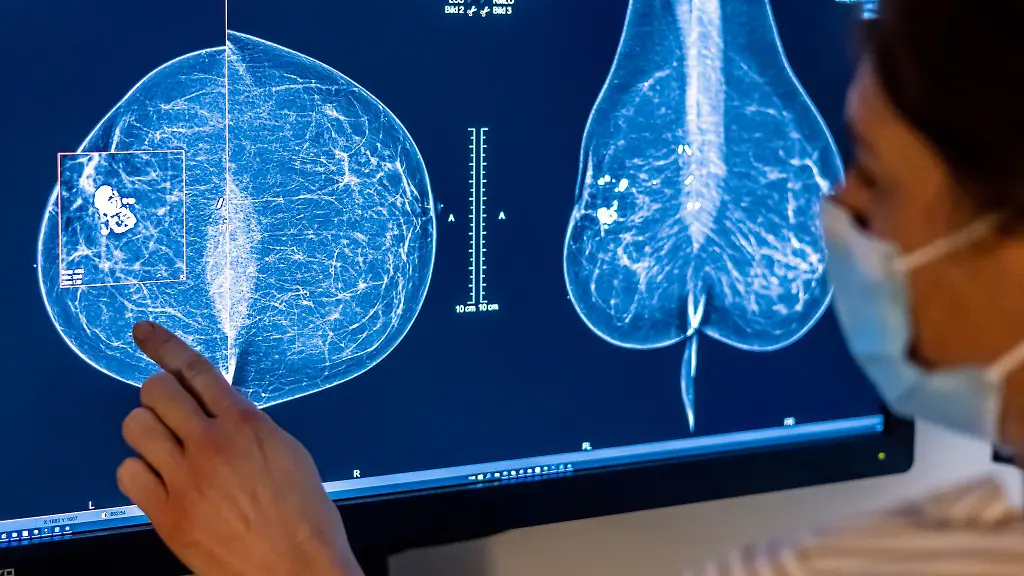

Berlin (dpa/bb) - In Berlin und Brandenburg nimmt nur etwa die Hälfte der eingeladenen Frauen am Mammographie-Screening teil. "Das ist deutlich unter der WHO-Empfehlung von 70 Prozent", sagt Katja Siegmann-Luz, Leiterin des Referenzzentrums Mammographie Berlin. Dabei gelte das deutsche Screening-Programm als eines der besten in Europa – zertifiziert und regelmäßig überprüft.

Das Mammografie-Screening für Frauen trägt einer Studie zufolge deutlich zur Senkung der Brustkrebs-Sterblichkeit in Deutschland bei. Das vor 20 Jahren eingeführte, von allen Krankenkassen angebotene Früherkennungs-Programm senkt die Todesfallzahlen und erhöht die Heilungschancen für erkrankte Frauen, wie das Bundesamt für Strahlenschutz (BfS) im Juli mitteilte. Unter den Teilnehmerinnen war die Brustkrebs-Sterblichkeit demnach über eine Nachbeobachtungszeit von bis zu 10 Jahren um 20 bis 30 Prozent geringer als bei den Nichtteilnehmerinnen.

Im Zuge des Programms können Frauen im Alter von 50 bis 75 Jahren alle zwei Jahre eine Röntgen-Untersuchung der Brust zur Früherkennung in Anspruch nehmen. "Unter den 50- bis 69-Jährigen nimmt jedes Jahr etwa die Hälfte der Eingeladenen am Mammografie-Screening-Programm teil", sagte BfS-Präsidentin Inge Paulini.